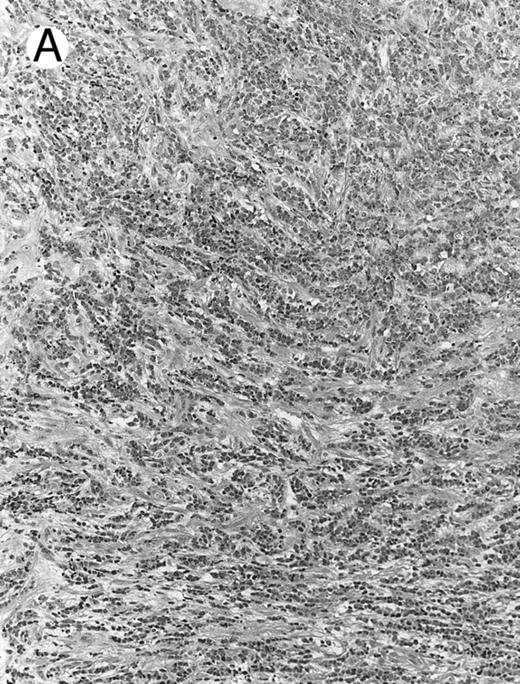

Lymph node biopsy of aggressive NK cell leukemia/lymphoma (case no. 37). There is a fairly monotonous, diffuse infiltrate of medium-sized cells with round nuclei. The neoplastic cells in this case resemble plasmacytoid monocytes.

There were very few to numerous granular lymphocytes in the peripheral blood. Some of the granular lymphocytes were indistinguishable from normal large granular lymphocytes, with round nuclei, dense chromatin, and pale cytoplasm with fine azurophilic granules (Fig 5A). Some granular lymphocytes had larger nuclei with more open chromatin and distinct nucleoli (Fig 5B); occasional nuclei could show indentations. The azurophilic granules were sometimes large and coarse. There were also circulating normoblasts and immature myeloid cells. Marrow involvement ranged from subtle to extensive. In histologic sections, irrespective of site, there was a monotonous infiltrate of medium-sized cells with round nuclei and fairly condensed chromatin (Fig 6). Karyorrhexis was prominent. The infiltrate was diffuse, interstitial, or angiocentric.